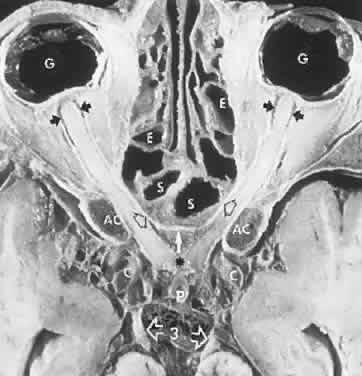

CONGENITAL HAMARTOMA SYNDROMES

The “neurophakomatoses” are a diverse group of disorders nosologically related by the presence of hamartomatous lesions, and, indeed, the term “hereditary hamartomatosis” is a more accurate description. However, whereas neurofibromatosis, tuberous sclerosis, and von Hippel-Lindau disease are transmitted with irregular dominance and considerable variation in penetrance, no hereditary basis of Sturge-Weber or angio-osteohypertrophy (Klippel-Trenaunay-Weber) syndrome has been established.